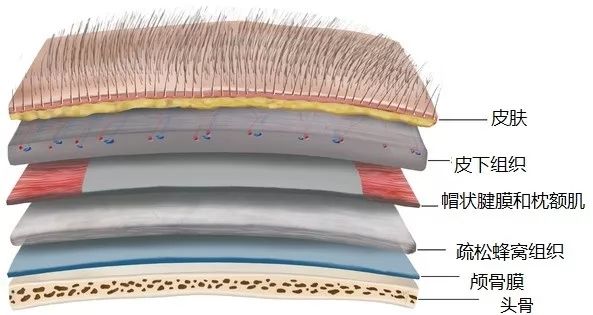

我们从头的外面开始。生物学研究有一点好,很多研究让人看了很有满足感,而脑本身有很多让人很满足的东西,其一就是人的头部其实跟个俄罗斯套娃一样。

我们的理解是,最外面是头发,下面是头皮,然后就是头部。其实不是这样的,头皮和头骨之间其实隔了19层东西。